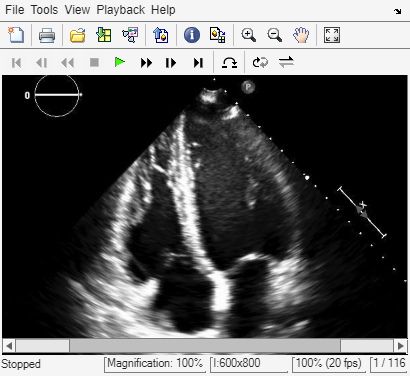

Display Ultrasound Series as Video

Open the Video Viewer app to view the ultrasound series as a video by using the implay function. The implay function automatically sets the frame rate using the FrameTime property of medImg.

implay(medImg)